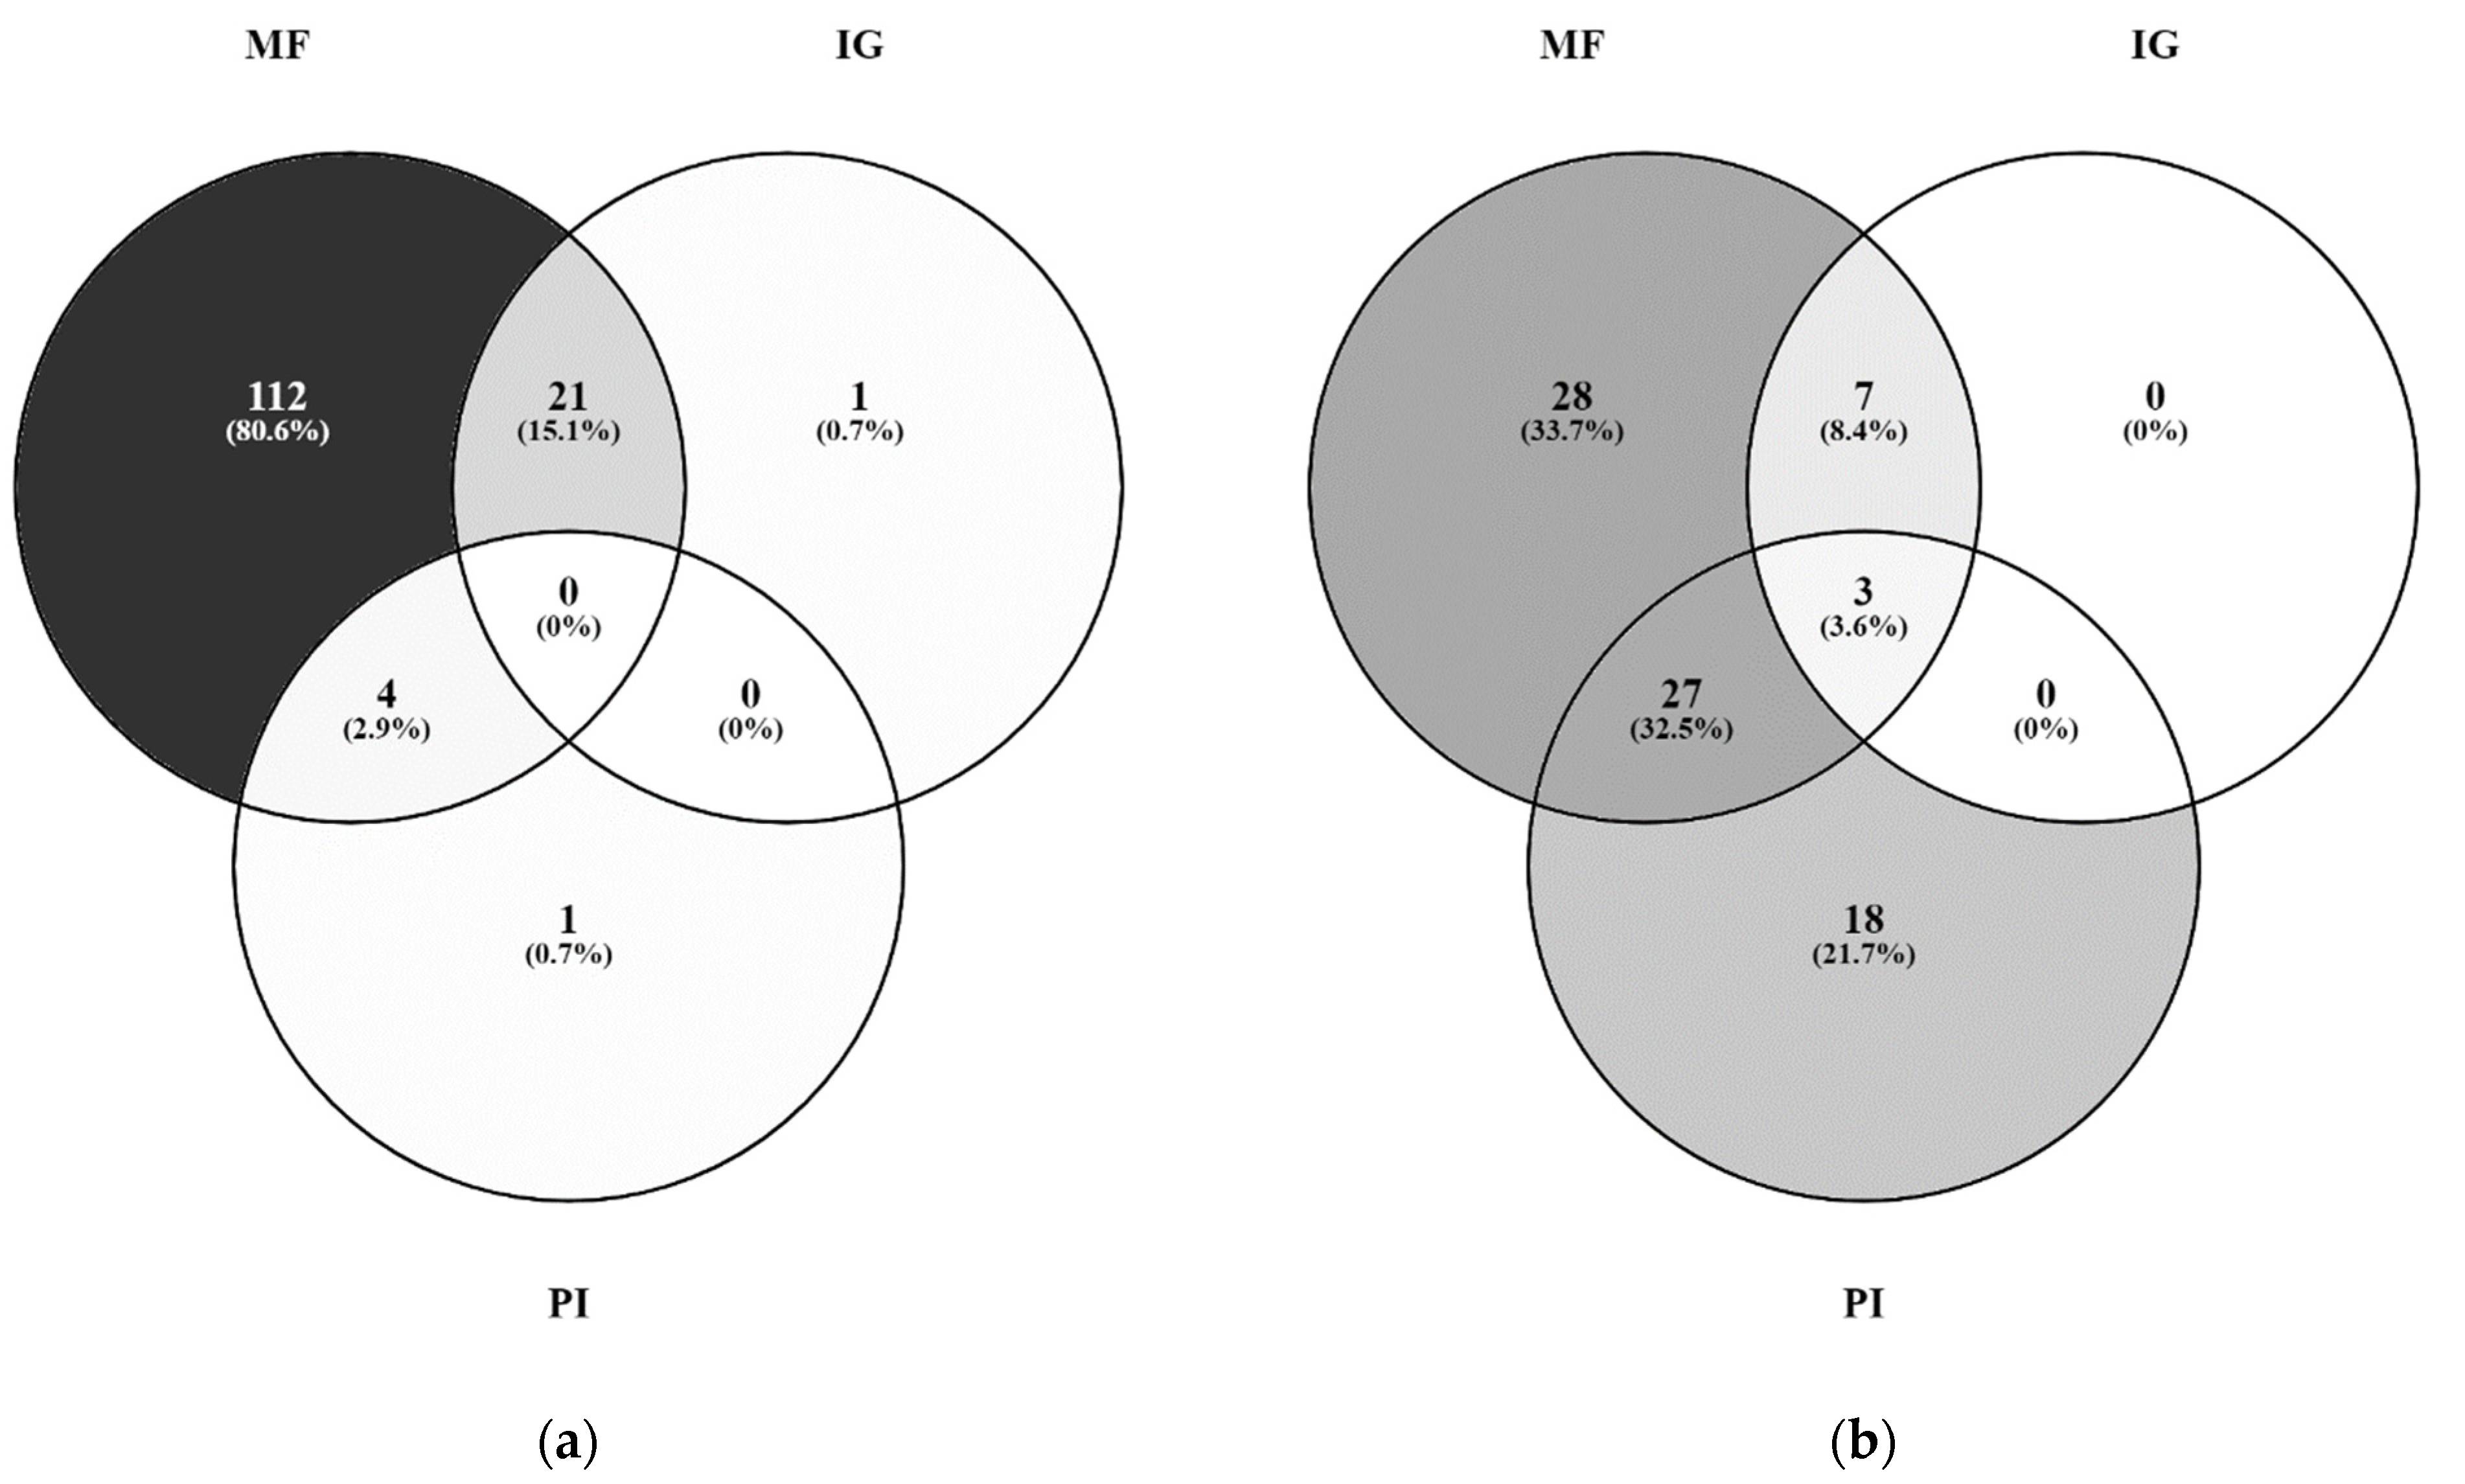

2.2. Radiological Findings

| Ductal growing pattern [%] | 2 | 33 | <0.001 | 0.446 | <0.001 | 16.17 | 3.07–85.06 | |

| Obstruction bile ducts [%] | 25 | 48 | 0.001 | 0.237 | ||||

| BilIn/IPNB [%] | 0/0 | 64/ 11 | <0.001 | 0.731 | <0.001 | 91.69 | 5.71–1472.03 | |

| Mass-forming [%] | 99 | 78 | <0.001 | 0.342 | ||||

| Intraductal-growing [%] | 15 | 12 | 0.156 | |||||

| Periductal-infiltrating [%] | 3 | 57 | <0.001 | 0.605 | ||||